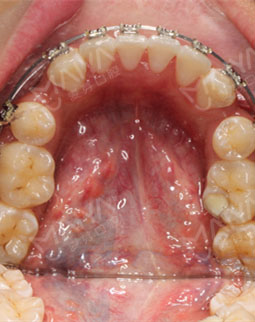

2017/04/22 矫正结束前

摘牙套前最后的一次拍照了,先看看牙,整齐啦!医生说等完全排齐后我就直接可以脱掉这些金属的东西了,想想好开心,吃盘龙虾奖励自己~~